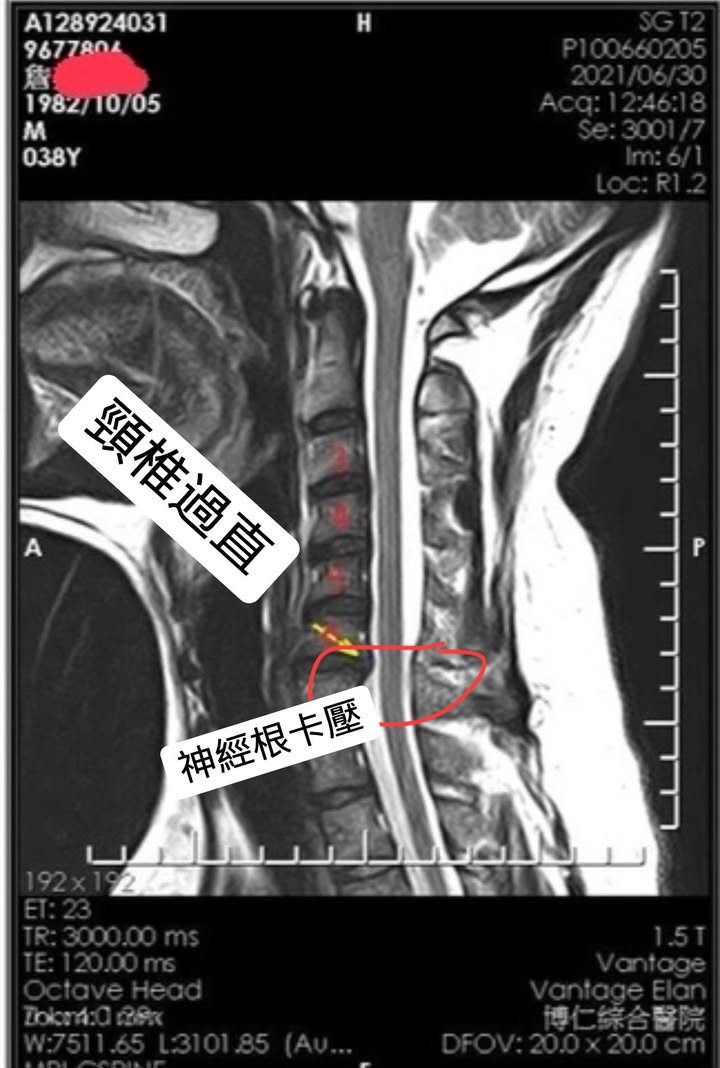

Cervical Spine Treatment Cases 頸椎治療案例 頸椎過直會導致肩膀酸痛嗎?中醫微創針刀療法成功改善頸椎弧度 2021.11.03 頸椎骨刺導致步態不穩、半身麻痛,一定要開刀嗎?中醫針刀治療100天改善實例公開 2021.10.07 冷水刺痛全身、下肢異常竟源自頸椎壓迫?MRI對比揭示非手術療法改善實證 2021.10.08 伏地挺身突然做不到?竟是C6C7頸椎壓迫導致神經肌力減退!中醫微創療法10週改善 2021.09.11 低頭族小心!頸椎滑脫竟導致長期頭痛肩痛與睡眠障礙|12次中醫微創治療成功矯正滑脫 2021.07.16 醫案實證:術後再發的脊髓壓迫症也能靠中醫療法改善 2021.07.10 手術後腳還是麻?頸椎開刀半年症狀未解,靠中醫微創8次改善右腳無力與手麻! 2021.06.30 狂送急診四次竟查不出病因!胸悶心悸原來是頸椎壓迫,靠針刀微創13次改善 2021.06.09 後縱韌帶鈣化壓迫脊髓!步態不穩、手腳麻木竟可逆轉?14週22次針刀治療真實見證 2021.05.06 什麼是中樞型脊髓型頸椎病?症狀、診斷與治療全解析 2021.05.28 神經根型頸椎病症狀解析:肩麻、手痛與肌肉萎縮 2021.04.16 嚴重心悸胸悶竟是頸椎問題!交感神經型頸椎病針治2次症狀明顯改善|真實病例與患者疼... 2021.04.07 從心悸胸悶到手麻夜痛難眠,她竟是頸椎壓迫!真實MRI對比見證中醫逆轉勝療效 2021.04.04 從手腳無力到步態不穩,他竟是頸椎脊髓型壓迫!三個月密集針刀療法逆轉勝|台北蔡大哥... 2021.03.31 頸椎椎間盤突出要一次動四節嗎?手術vs.保守治療完整解析 2021.03.27 ← 上一頁 2 3 4 5 6 下一頁 →